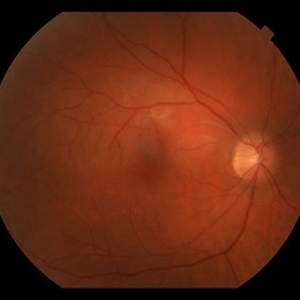

Background: 46-year-old WF with CML (stable on Sprycel) saw her PCP for headaches without known cause; Headaches worsened and became confused, disoriented, off balance, and impaired short term memory. Heme-oncology ordered MRI that showed abnormal signal in the cerebellum and other parts of the brain, and LP has elevated protein. LP did show positive tau test, but fortunately, was a false positive for CJD. IV and PO steroids started and symptoms improved. MRI showed much improvement one month since starting steroids. 3 weeks later had a scotoma in right eye and eye doctor did not find anything at that time to cause it. Tinnitus developed (and some intermittent vertigo before that) and ENT referred back to eye doctor, who then referred the patient to Dr. Zocchi. He found a CWS and BRAO superotemporally OD (see photo), and bilateral arteritis. She had some additional work-up for vasculitis. Given the retinal arteritis, cochlear issues, and MRI findings, Dr.Zocchi suspected Susac's Syndrome. She was started on multiple regimens including prednisone, IVIG, azathioprine, and MTX, and has had the best reponse to IVIG. She is stable and doing well with 20/20 vision in both eyes.

Photographer: Macey Highfill

Imaging device: Topcon

Condition/keywords: Susac's syndrome